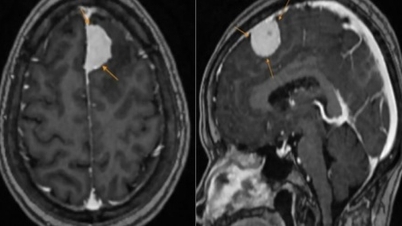

| CTA snímek. Levý snímek: Normální osoba, dvě větve koronární tepny vycházející ze dvou samostatných kořenů. Pravý snímek: Dvě větve koronární tepny pacienta vycházející ze společného kořene. |

Výsledky počítačové tomografie (CT) ukázaly, že pacient má vzácnou vrozenou abnormalitu zvanou jediná koronární tepna typu LII-B. Tato abnormalita způsobuje, že levá i pravá koronární tepna vycházejí z jednoho kořene namísto dvou samostatných kořenů.

Normálně má srdce dvě koronární tepny, levou a pravou, které vycházejí ze dvou různých míst na koronárním sinu aorty a zásobují srdeční sval krví. U lidí s touto vadou však existuje pouze jedna koronární tepna vycházející z jednoho místa a poté se větví a zásobuje celé srdce.